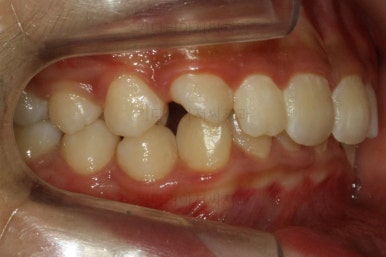

그 다음 문제는 왼쪽 송곳니 부분(붉은색 동그라미)이 유치가 남아있고, 영구치가 매복되어 있는 경우였어요.

화살표를 보시면 송곳니가 나오지 못하고 뼈속에 묻혀 있는 것을 볼 수 있습니다.

이를 "매복치" 혹은 "매복치아" 라고 표현하는데 이넞ㅂ한 치아들의 뿌리를 녹인다거나 아예 다른 방향으로 간다거나 하는 문제가 생길 수 있기 때문에 조기에 발견하고 치료를 해줘야 합니다.

상태를 보면 옆에 있는 안그래도 작은 왜소치의 뿌리를 건드리는 양상으로 있어서 좀 더 정밀한 3차원 CT를 찍어 보기로 했습니다.

우선 유치를 뽑고 시간을 보내보니 자연스럽게 송곳니가 나왔어요. 매우 다행이었어요.

송곳니가 어느 정도 나온 것을 확인한 후, 교정장치를 부착해서 교정치료를 들어갔습니다.

부산교정치과 키다리아저씨치과에서 치료한 이번 치료의 전후사진을 비교해 볼게요.

왼쪽이 치료 전, 오른쪽이 치료 후 모습입니다.